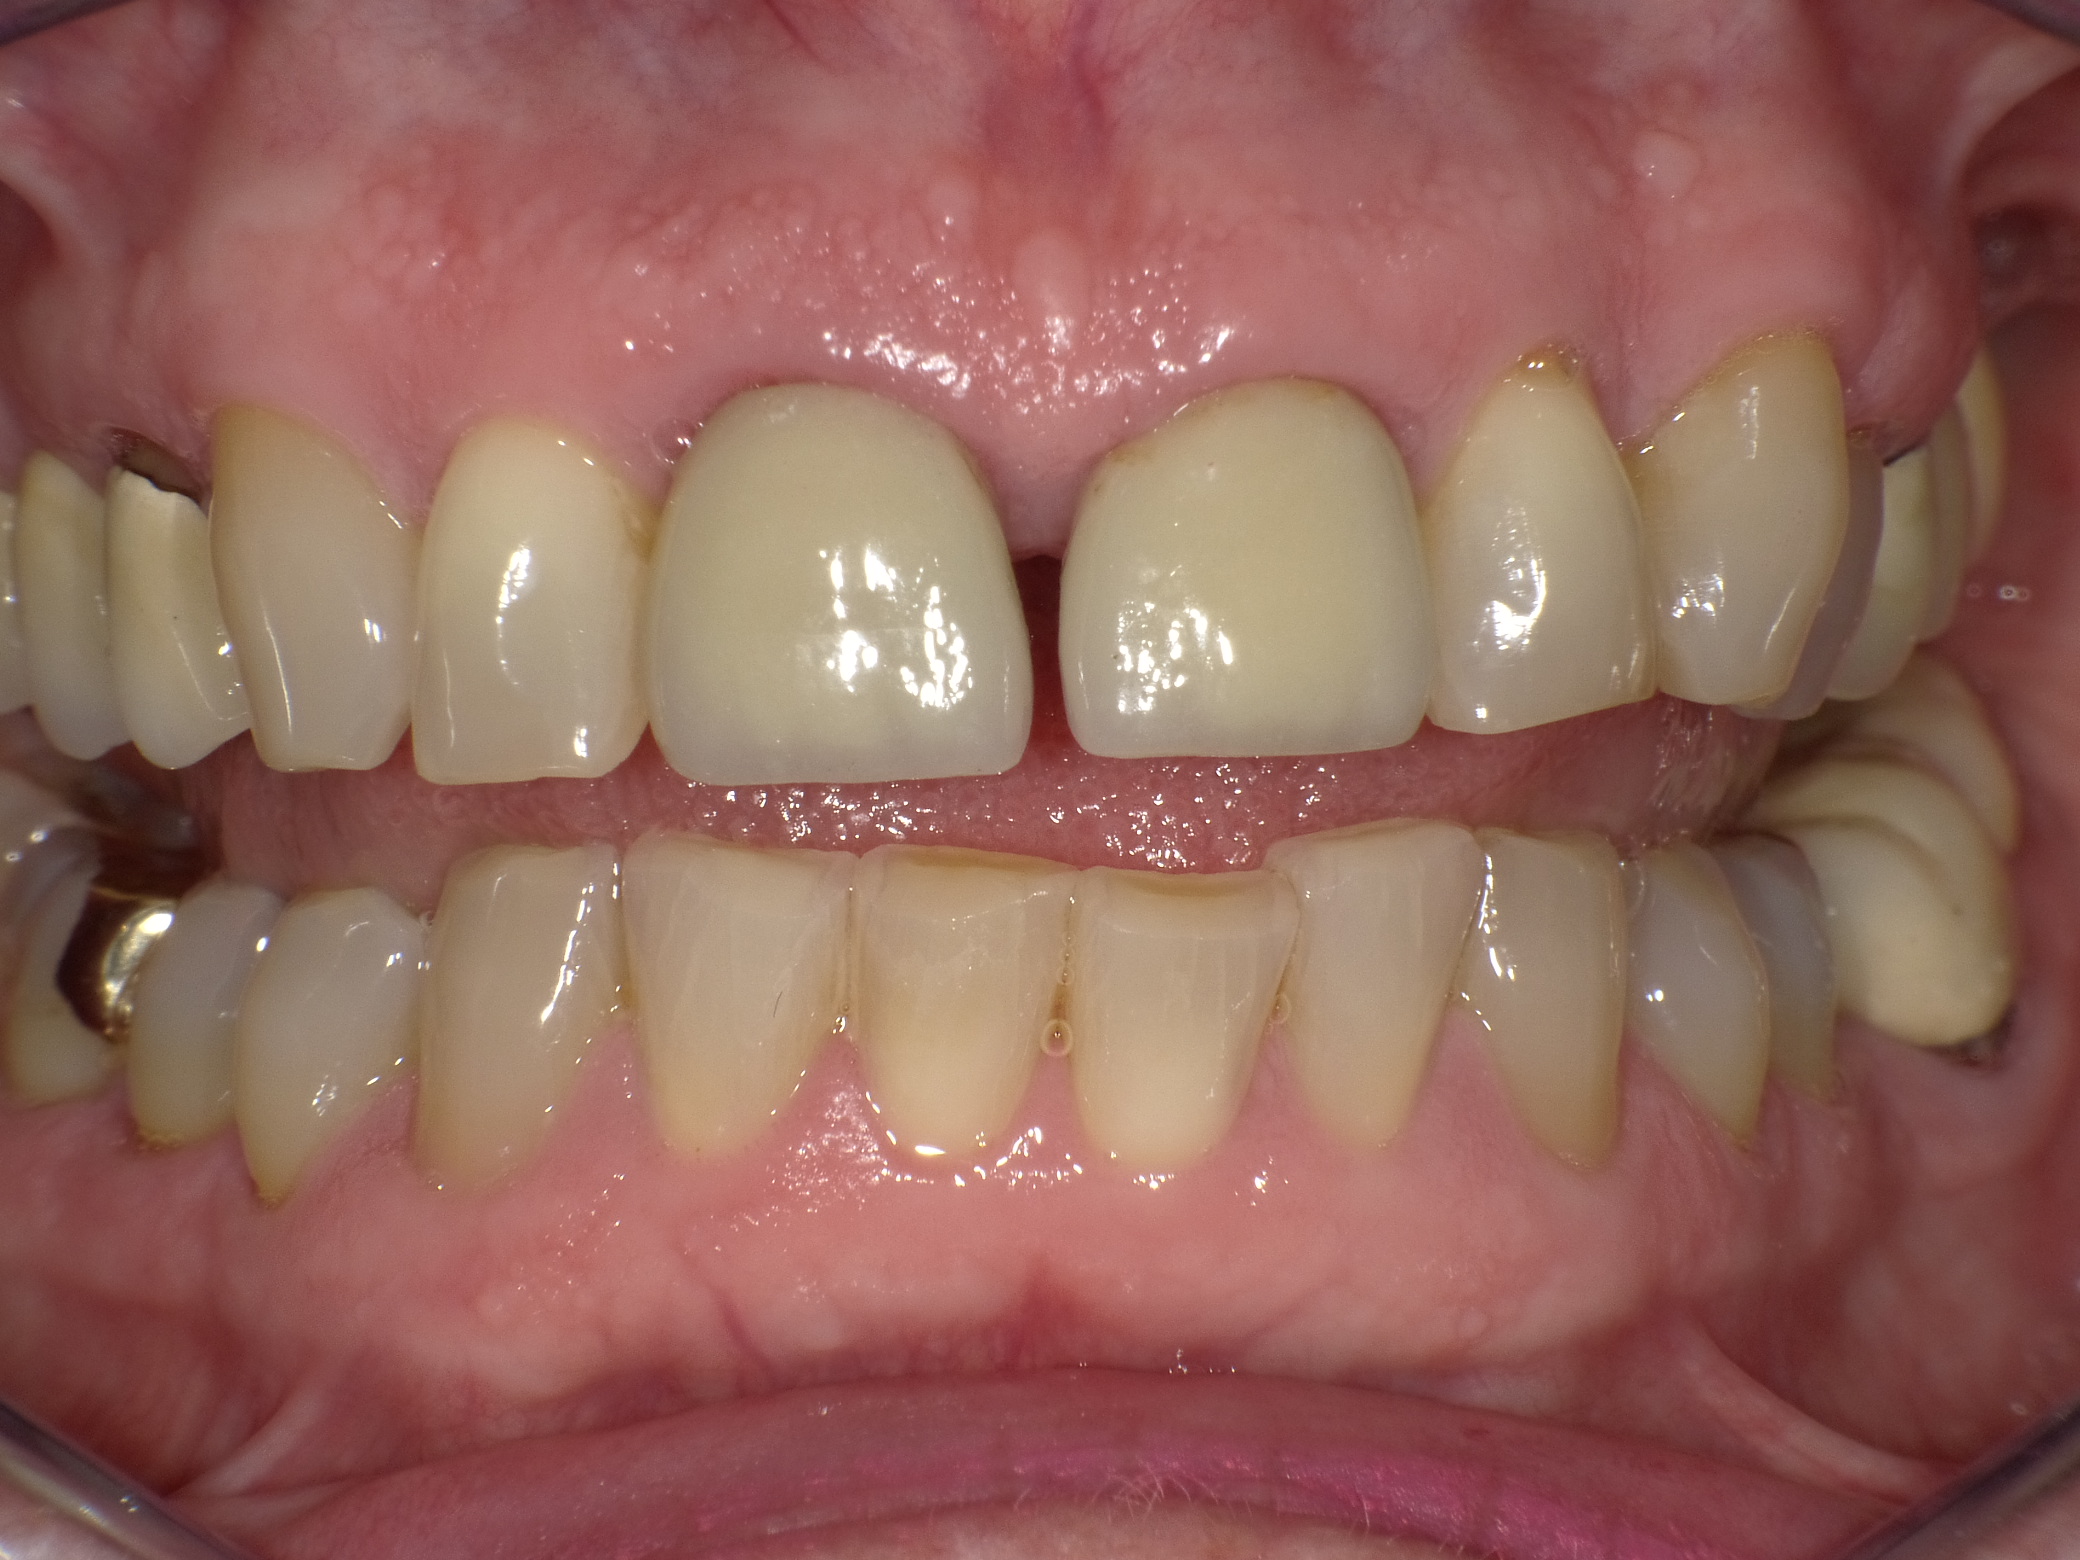

Abradierte, gelbliche Zähne mit vielen Kunststoff-Füllungen und Kronen, die der Patientin nicht gefallen haben

Vorher: Abradierte, gelbliche Zähne mit vielen Kunststoff-Füllungen und Kronen, die der Patientin nicht gefallen haben

Leuchtende Zähne durch vollkeramische Veneers und Teilkronen in nur 2 Terminen

Nachher: Leuchtende Zähne durch vollkeramische Veneers und Teilkronen in nur 2 Terminen